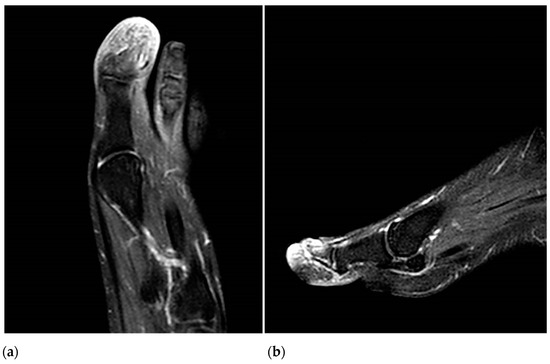

The CT angiography did not report the presence of stenosis, atheroma, or signs of thrombosis in the arterial system of the affected foot; however, a decrease in the diameter of the posterior tibial artery of the right limb (at the level of the medial malleolus) was observed. There was no filling of the plantar arteries, a fact that does not rule out the presence of thrombosis at this level. Magnetic resonance imaging revealed bone edema with inflammatory changes in the soft tissues of the distal phalanx of the left hallux (Figure 3a,b). Contrast-enhanced magnetic resonance imaging revealed diffuse uptake at the level of a distal phalanx, ruling out the possible existence of a cystic lesion or abscess related to local osteomyelitis. Abdominal ultrasound revealed no organic abnormalities.

Figure 3. T2-weighted coronal (a) and axial (b) MRI images show bone edema in the distal phalanx with inflammatory changes in the soft tissues that are more intense in the subungual region.